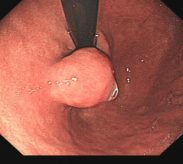

消化道早癌的病例展示(经内镜手术或活检证实):

胃角的腺癌

胃窦的微小腺癌